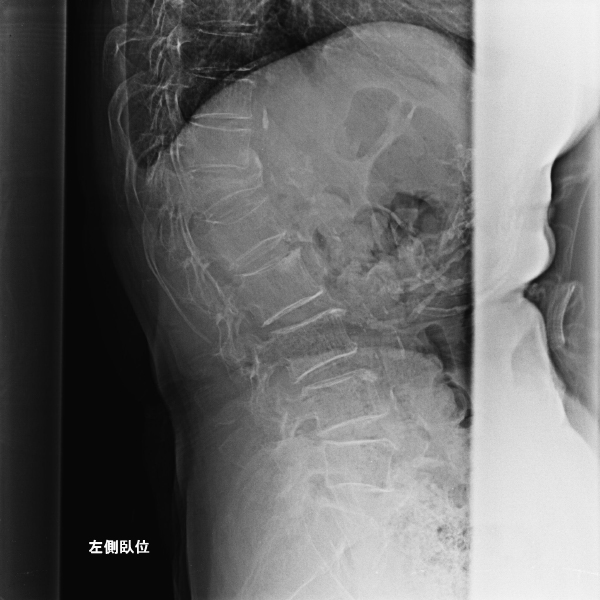

放射線科